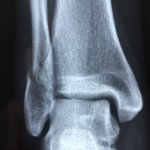

Stress fractures – The facts Stress fractures occur when there is a small hairline crack in the bone, usually in the lower limb. Common sites are the foot and shin, or tibia. Unlike common fractures, which are caused by a sudden impact, stress fractures are caused by overuse and are therefore most common in athletes…